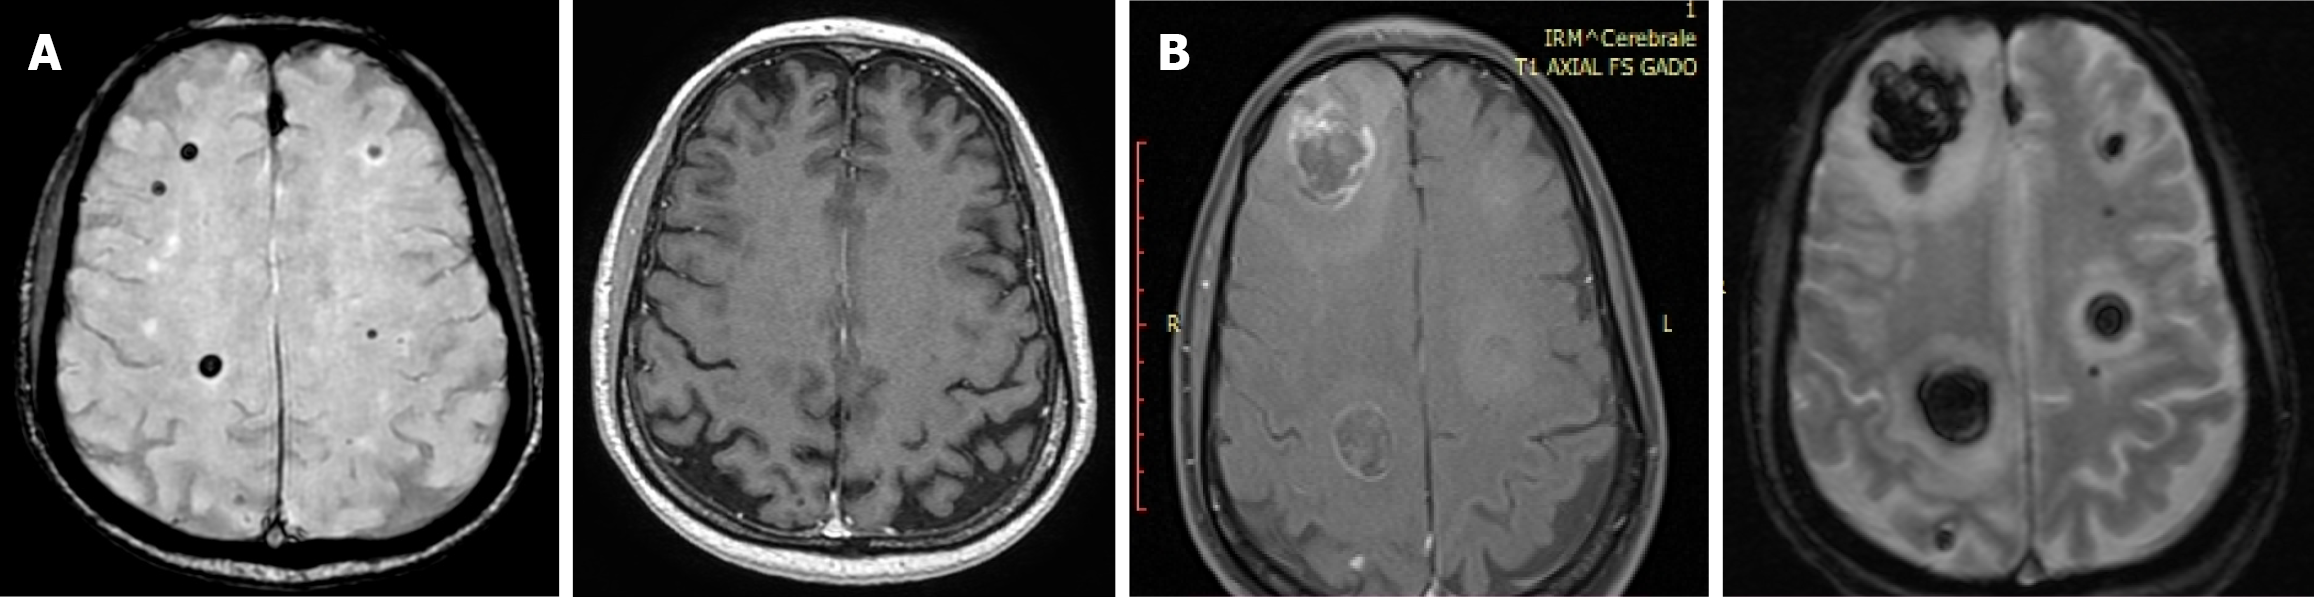

Figure 5 Magnetic resonance images from December 2024 and January 2025.

A: Axial magnetic resonance imaging (magnetic resonance imaging [MRI]; December 16, 2024): Right hemispheric nodular lesions (0.5 cm and 0.6 cm), no contrast enhancement pre- or post-contrast; B: Axial MRI (January 23, 2025): Marked lesion enlargement (2.0 cm and 2.5 cm) with minimal contrast enhancement.